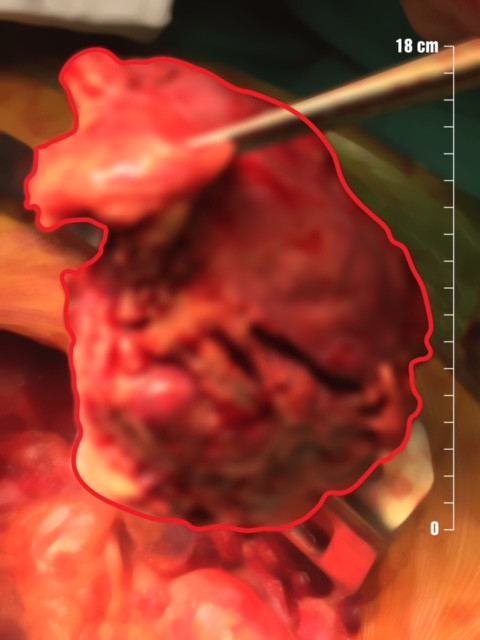

Sau khi phẫu thuật bóc tách, khối u được cắt bỏ toàn bộ cùng với màng ngoài tim và màng phổi trung thất bên trái. Tuy nhiên, vì khối u xâm lấn thần kinh hoành trái lâu ngày, mặc dù thần kinh hoành trái được giải phóng nguyên vẹn ra khỏi khối u, nhưng qua đánh giá trong mổ, cơ hoành trái của BN bị nhão và nhô rất cao hơn bình thường, các bác sĩ quyết định tạo hình làm căng cơ hoành (duplicature cơ hoành) nhằm tránh biến chứng suy hô hấp và không rút được máy thở sau mổ.

Khối u “khủng” của BN được lấy ra sau phẫu thuật